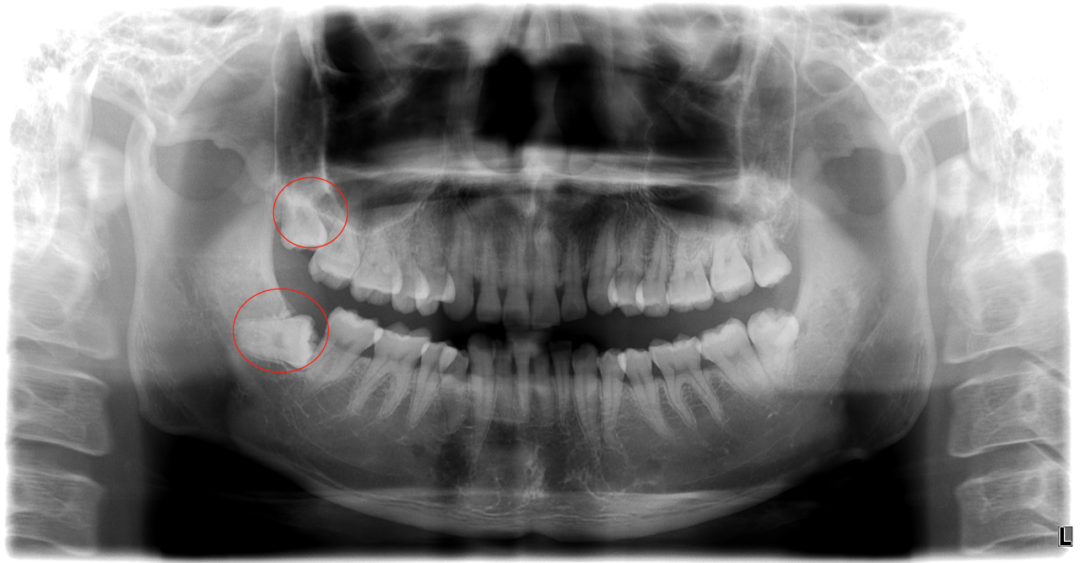

但她是埋伏阻生智齿

日前已经影响到神经

导致面部到颈部大片区域出现神经刺痛

水平阻生齿